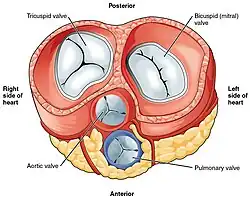

Válvulas

O coração possui quatro válvulas que regulam a passagem do sangue entre as suas cavidades. Existe uma válvula entre cada aurícula e ventrículo e uma válvula à saída de cada ventrículo.[7] As válvulas entre as aurículas e os ventrículos são denominadas válvulas auriculoventriculares. Entre a aurícula direita e o ventrículo direito situa-se a válvula tricúspide. Esta válvula apresenta três cúspides[23] ligados às cordas tendinosas e três músculos papilares, denominados anterior, posterior e septal, de acordo com a sua posição.[23] Entre a aurícula esquerda e o ventrículo esquerdo situa-se a válvula mitral. Esta válvula é por vezes denominada bicúspide, por ter dois cúspides, um anterior e um posterior. Estes cúspides também estão ligados pelas cordas tendinosas aos dois músculos papilares que se projetam da parede ventricular.[24]

Os músculos papilares estendem-se a partir das paredes do coração para as válvulas através de ligações cartilaginosas denominadas cordas tendinosas. Estes músculos impedem as válvulas de regredir quando se fecham.[25] Durante a fase de relaxamento do ciclo cardíaco, os músculos papilares estão igualmente relaxados e a tensão nas cordas tendinosas é reduzida. Assim que as cavidades do coração se contraem, também se contraem os músculos papilares. Isto cria tensão nas cordas tendinosas, o que ajuda a manter os cúspides das válvulas auriculoventriculares no lugar e impede-as de serem projetadas para as aurículas.[7][nota 4]

À saída de cada um dos ventrículos existem duas válvulas adicionais. A válvula pulmonar situa-se na base da artéria pulmonar. Esta válvula apresenta três cúspides que não se encontram ligados a quaisquer músculos papilares. Quando o ventrículo relaxa, o sangue flui da artéria regressando ao ventrículo. Este refluxo preenche a válvula em forma de bolsa, o que exerce pressão contra os cúspides, que se fecham para selar a válvula impedindo assim esse refluxo. A válvula aórtica situa-se na base da artéria aorta e também não se encontra ligada aos músculos papilares. Também apresenta três cúspides que se fecham com a pressão do sangue que regressa da aorta.[7]